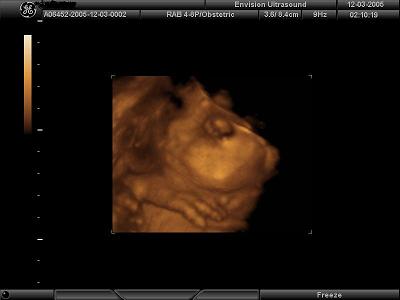

This was at 14 weeks Image Attachment(s):